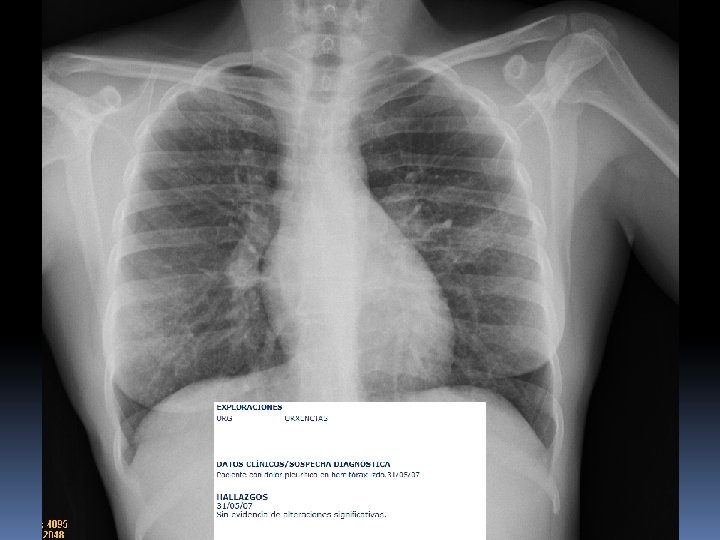

X 2007 Mujer 26 años Astenia, adelgazamiento 5 kg en 3 -4 meses. Nerviosa. Problemas de pareja. Hace 15 dias : tos seca y dolor en costado izquierdo por lo que acude a Urgencias del hospital. No fiebre termometrada. Dolor en costado Izquierdo de características pleuríticas. Auscultación normal. Sat 98%.